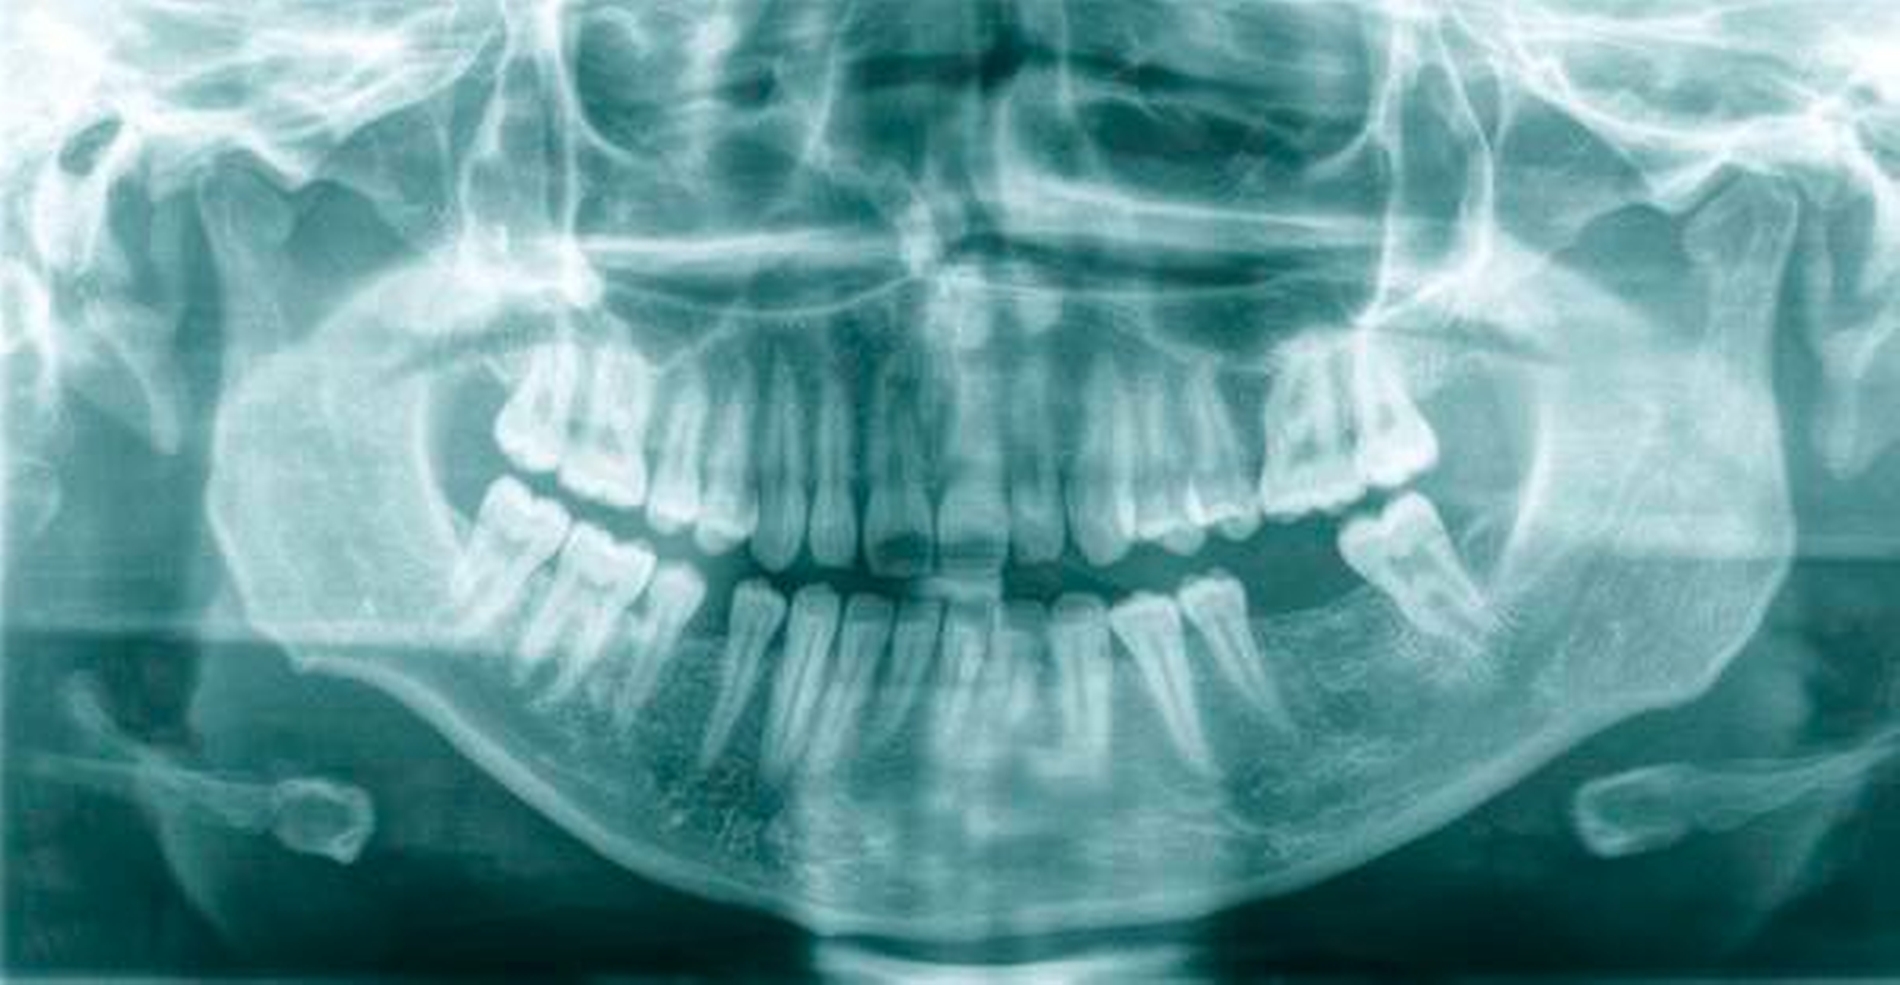

Auch radiologisch ließen sich keine Auffälligkeiten darstellen (Abbildung 1). Aufgrund der lang anhaltenden Persistenz und auf Wunsch der Patientin entschieden wir uns für eine chirurgische Inspektion mit Option auf Entfernung des Tumors. Analog zur Schnittführung der Weisheitszahnentfernung wurde das Gewebe Regio 36 marginal mit einer mesialen und distalen Entlastung eröffnet und ein Spaltlappen gebildet. Bis zur verdächtigen Raumforderung wurde stumpf mit der Schere präpariert (Abbildung 2), wobei sich die Läsion schließlich als abgekapselte Struktur darstellte, die sich sehr gut aus dem umliegenden Gewebe entfernen ließ. Das klinische Erscheinungsbild der Raumforderung entsprach am ehesten der eines Lipoms (Abbildung 3). Nach kompletter Entfernung der Raumforderung (Abbildung 4) wurde die Wunde mit Nähten speicheldicht verschlossen (Abbildung 5).